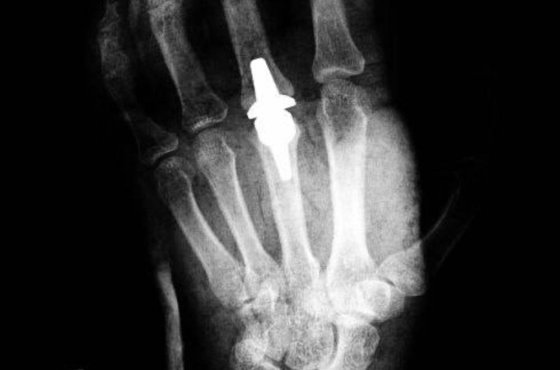

Спектр наших возможностей стал очень большим. Помимо таблеток используется целый ряд внутрисуставных введений - гиалуроновой кислоты в сочетании с хондроитином, плазмы, обогащенной тромбоцитами (PRP-терапия), стволовых клеток, полученных из жировых клеток самого пациента. Применяются маленькие, органсохраняющие операции, которые позволяют отложить проведение эндопротезирования. Грамотно комбинируя эти методы лечения, мы в большинстве случаев добиваемся длительных ремиссий.

Антон Наумов: Тут есть несколько мифов. Один из них - что эндопротезирование является сложной, "кровавой" операцией. Оно давно перестало быть таким. Более того, оно признано самой лучшей операцией за всю историю хирургии, поскольку вернуло к жизни миллионы людей, и не только с остеоартритом, но и с переломом шейки бедра. Оно стало рутинной операцией типа удаления аппендикса. Могу сказать точно: если вам больше 60 лет и вы лечили сустав полгода-год, но все равно сохраняется боль, эндопротезирование продлит и ваши физические возможности, и жизнь. Это очень хорошо отработанная операция, которая дает очень мало осложнений, и они чаще всего связаны с несоблюдением рекомендаций врачей.